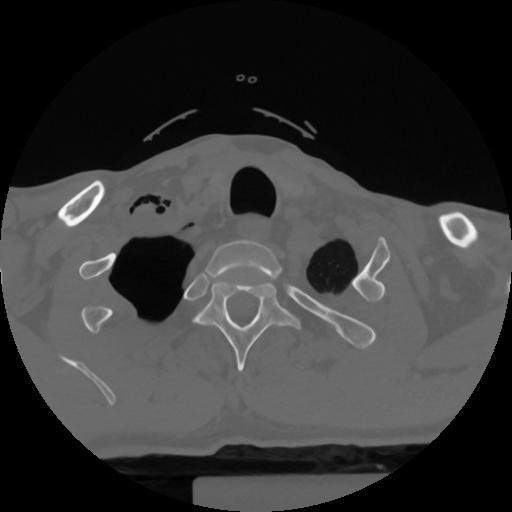

12 P.BLANDAS,,Vol,0.5,P.BLANDAS,,